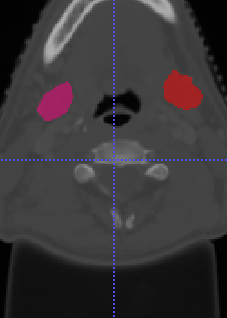

In Chapter 6, we propose an end-to-end, atlas-free 3D convolutional deep learning framework for fast and fully automated whole-volume HaN anatomy segmentation [115]. Our deep learning model, called AnatomyNet, segments OARs from head and neck CT images in an end-to-end fashion, receiving whole-volume HaN CT images as input and generating masks of all OARs of interest in one shot. AnatomyNet is built upon the popular 3D U-net architecture, but extends it in three important ways: 1) a new encoding scheme to allow auto-segmentation on whole-volume CT images instead of local patches or subsets of slices, 2) incorporating 3D squeeze-and-excitation residual blocks in encoding layers for better feature representation, and 3) a new loss function combining Dice scores and focal loss to facilitate the training of the neural model. These features are designed to address two main challenges in deep-learning-based HaN segmentation: a) segmenting small anatomies (i.e., optic chiasm and optic nerves) occupying only a few slices, and b) training with inconsistent data annotations with missing ground truth for some anatomical structures. We collect 261 HaN CT images to train AnatomyNet, and use MICCAI Head and Neck Auto Segmentation Challenge 2015 as a benchmark dataset to evaluate the performance of AnatomyNet. The objective is to segment nine anatomies: brain stem, chiasm, mandible, optic nerve left, optic nerve right, parotid gland left, parotid gland right, submandibular gland left, and submandibular gland right. Compared to previous state-of-the-art results from the MICCAI 2015 competition, AnatomyNet increases Dice similarity coefficient by 3.3% on average. AnatomyNet takes about 0.12 seconds to fully segment a head and neck CT image of dimension , significantly faster than previous methods. In addition, the model is able to process whole-volume CT images and delineate all OARs in one pass, requiring little pre- or post-processing. We demonstrate that our proposed model can improve segmentation accuracy and simplify the auto-segmentation pipeline. These contributions are released as an open-source software package called AnatomyNet, which is publicly available555https://github.com/wentaozhu/AnatomyNet-for-anatomical-segmentation. Portions of this chapter were published as part of [115].

- [121] W. Zhu and X. Xie. Adversarial deep structural networks for mammographic mass segmentation. arXiv:1612.05970, 2016.